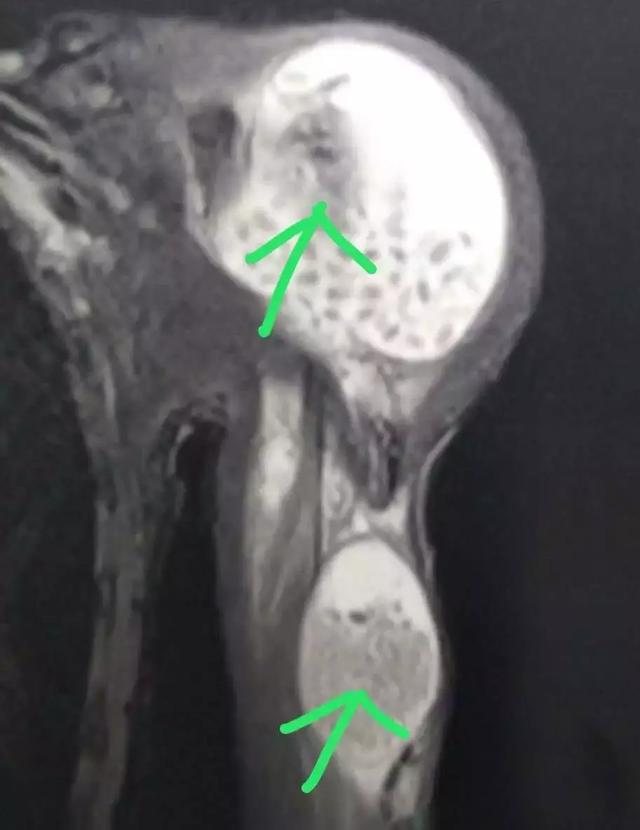

一个多月前,40来岁的赵哥(化名)发现自己的左肩关节肿起来了,肩部无力,抬不起来,并伴随有疼痛感,怀疑是肩关节炎,吃了药后一直没有好转,来到湘雅医院骨科就诊后,通过核磁共振影像,发现赵哥的左肩关节里面布满了一粒粒的“米粒”样的颗粒。

核磁共振影像图

手术进行了1个多小时,清除出来的颗粒物有一盆,数量多达上百颗,这些跟米粒大小的颗粒物,质软,实心,据了解,这种米粒体于1895年由Riese在关节结核中首次描述,目前对其形成过程仍存在争议,可能是滑膜炎症、增生以及蜕变的产物,这些脱落的滑膜在滑液里被纤维蛋白包裹形成了米粒体,或者是在滑液中独立合成。米粒体由纤维蛋白、网状蛋白及胶原等组成。其诊断主要依靠核磁共振(MRI),但应关注与无钙化的滑膜软骨瘤病鉴别诊断。